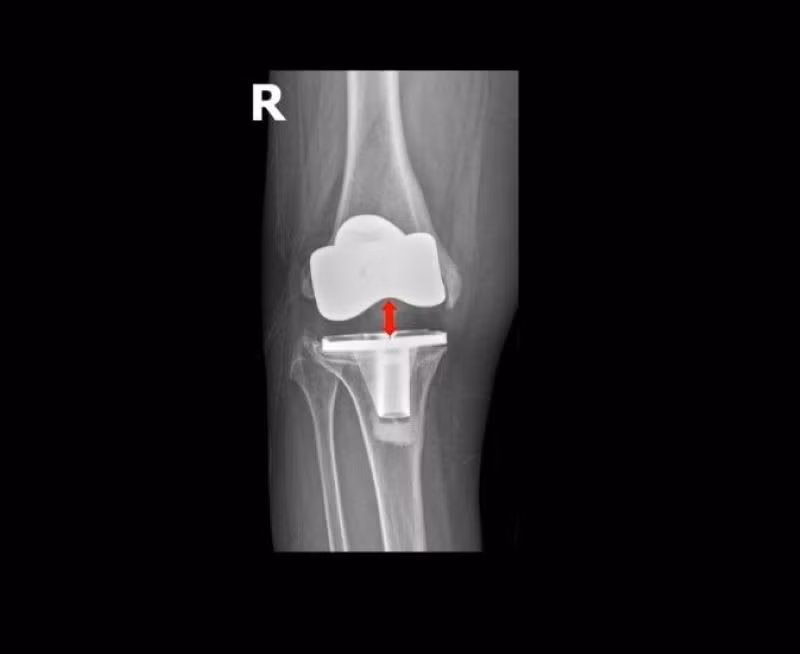

Khớp gối nhân tạo lỏng lẻo, di lệch khỏi ổ khớp - Ảnh BVCC

Khớp gối nhân tạo lỏng lẻo, di lệch khỏi ổ khớp

Chỉ sau gần 5 năm phẫu thuật, cấu phần lồi cầu đùi nhân tạo (phần kim loại bao bọc đầu dưới xương đùi) đã lún vào lồi cầu trong xương đùi gần 2cm, khiến khớp gối lệch khỏi vị trí ban đầu, mất vững kèm mất cân bằng mô mềm quanh khớp dẫn đến bệnh nhân không đi lại được.